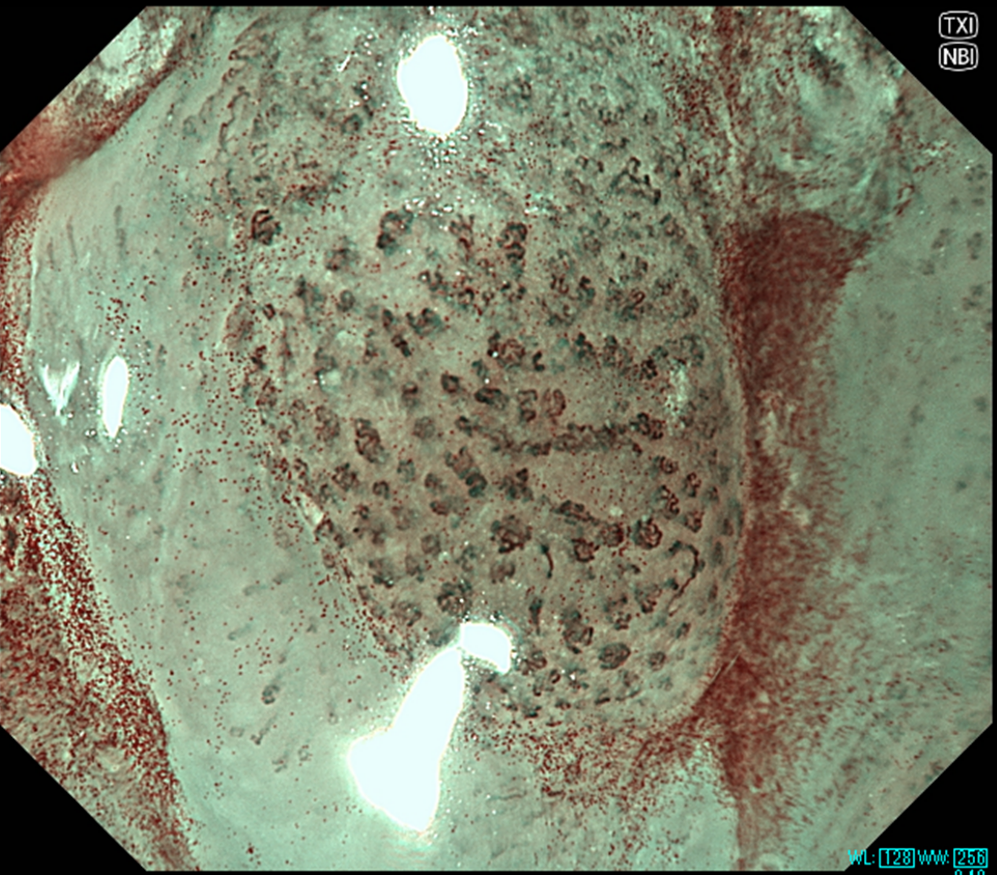

(2組)食道表在癌の拡大観察時の画像

NBI(左)よりもNBI+TXI(右)ではIPCLが強調されており、より明瞭に観察される。